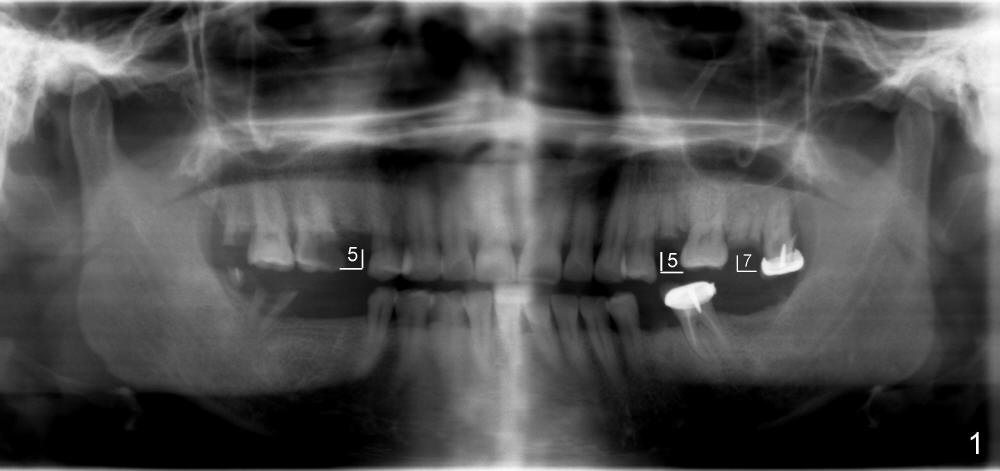

颊舌侧骨头宽度也很充足,所以使用钻头形成植牙床(图三:三点五乘十七毫米钻头(D)),之后植入四点五乘十七毫米种植体(图四),其实一个植牙花的时间比两个还长,为什么?